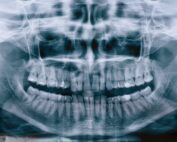

¿Qué es la mordida cruzada posterior y cómo se trata?

¿Qué es la mordida cruzada posterior? La mordida cruzada posterior [...]